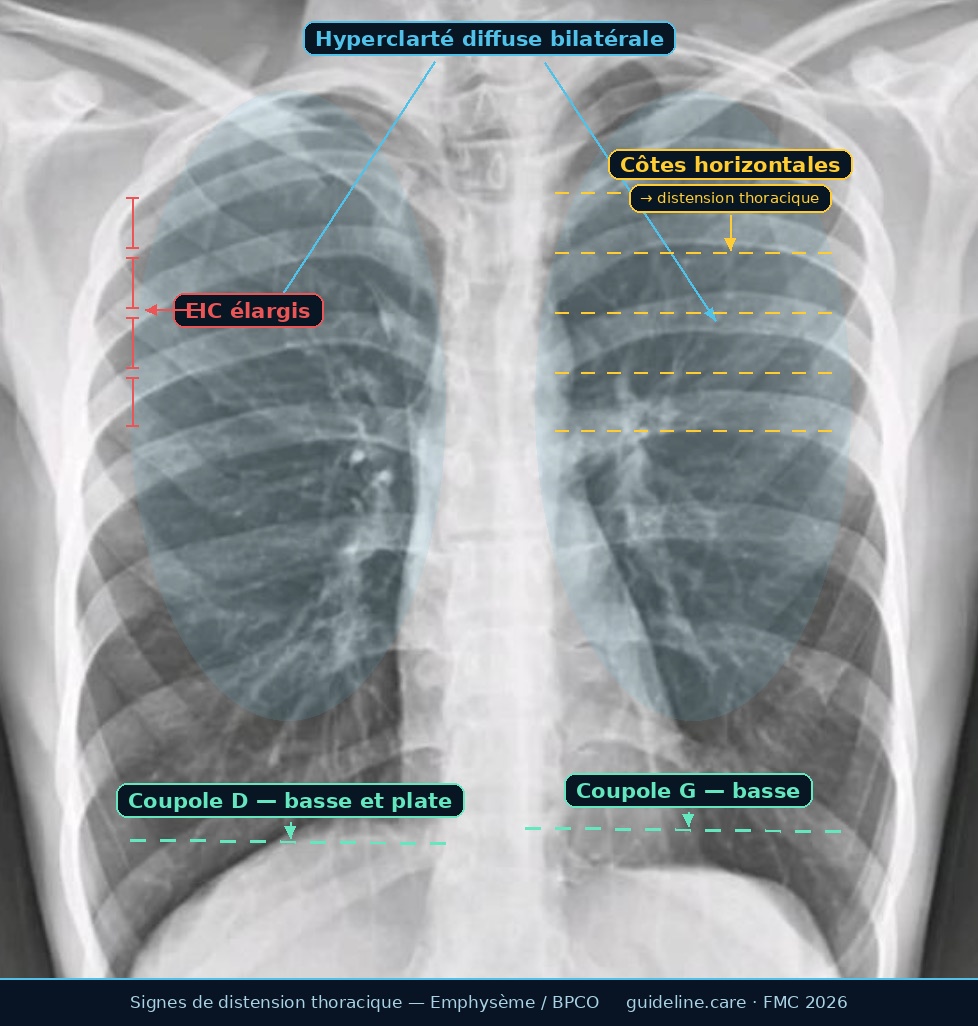

RP annotée 👇

Réponse B: Vrai. La radiographie de Mr M. présente les 4 signes cardinaux de distension thoracique liés à l'emphysème :

Ces signes traduisent un emphysème, complication fréquente de la BPCO. Attention ! la radio seule ne confirme pas le diagnostic — elle oriente seulement.

Une radiographie thoracique normale se caractérise par des coupoles diaphragmatiques arquées et bien visibles, des côtes à orientation oblique descendante, un parenchyme pulmonaire de densité homogène avec une vascularisation visible jusqu'aux 2/3 externes, et un rapport cardiothoracique < 0,5. Ici, les 4 signes de distension sont présents et constituent une anomalie radiologique significative.

☝ Attention : Une radio dite « normale » n'exclut pas une BPCO débutante => Limite de la radio : sensibilité < 50% pour la BPCO débutante. La spirométrie reste indispensable et ne peut pas être remplacée par la radiographie.